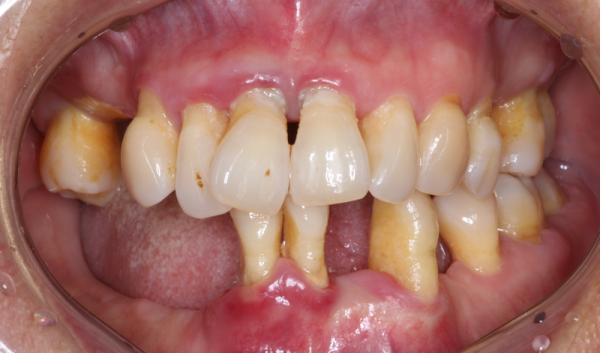

치료 전과 치료 후는 이렇게 달라집니다.